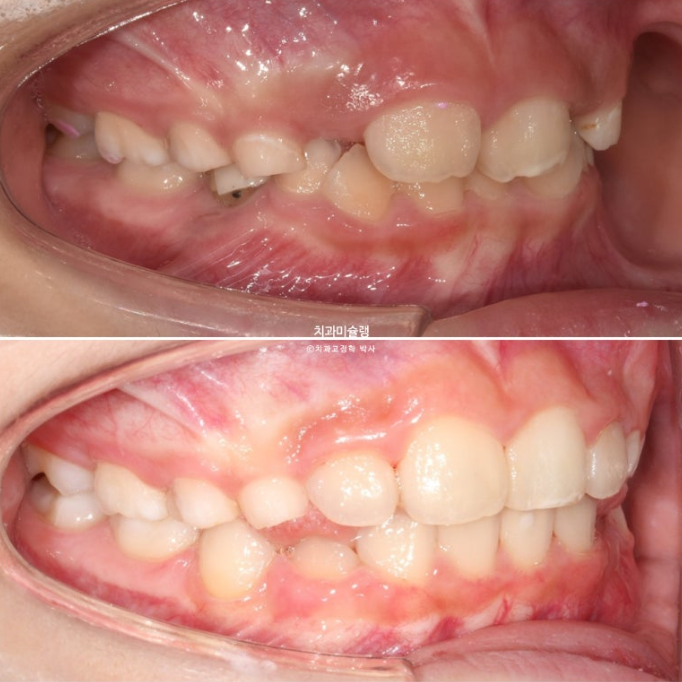

앞니 두 개 높낮이 차이, 앞니가 깊게 물리는 과개교합이 보입니다.

앞니 네개 중 옆 앞니 즉 측절치가 나올 공간이 좁습니다.

과개교합은 개선되었고 측절치 나올 공간을 악궁확장으로 미리 벌려줬기 때문에 측절치는 잘 내려왔습니다.

중심선 불일치 개선과 송곳니 나올 공간을 좀 더 확보하기ㅏ 위해서 추가장치 제작에 들어갑니다.

중심선은 잘 맞아졌고 과개교합은 더 개선이 되었습니다.

송곳니는 잘 올라오고 있습니다.

이제 전 후 비교 보겠습니다.

23.10~25.08